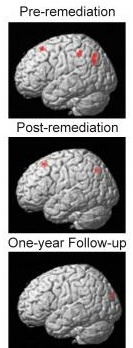

The new findings showed that many of the poor readers' brain areas activated at near-normal levels immediately after remediation, with only a few areas still underactive. However, at the one year follow-up scan, the activation differences between good and poor readers had nearly vanished, suggesting that the neural gains were strengthened over time, probably just due to engagement in reading activities.

CCBI research fellows Ann Meyler and Tim Keller measured brain activity patterns by examining blood flow to all of the different parts of the brain while children were reading. Those measurements showed that prior to the remediation, the parietotemporal areas were significantly less activated among the poor readers than in the control group.